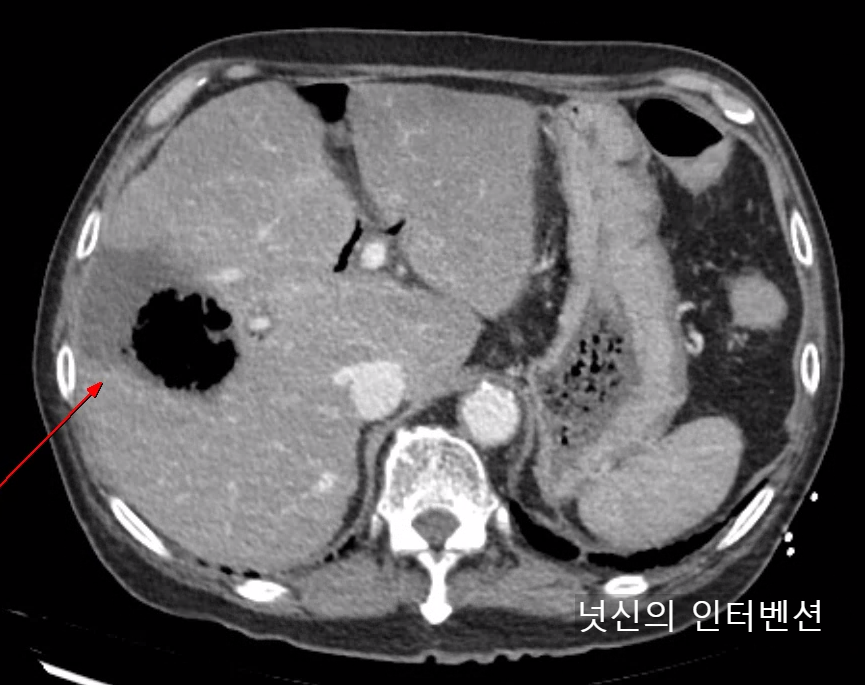

| 수술 후 액체 저류 (Post operative fluid collection) (0) | 2024.03.31 |

| 악성 복수 (Malignant ascites) (0) | 2024.03.31 |